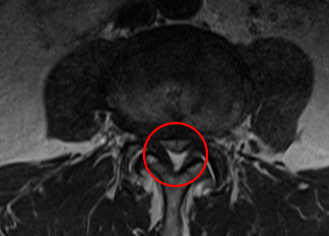

治療後

術後から1か月目の検診時には、左側のお尻の痛みが無くなり、痺れも軽くなったと言っていました。術後のMRI画像でも、しっかりと減圧されていていることを確認しました。しかし切開した箇所が一部癒着不全を起こしていたため、処置を行いました。再縫合から11日目の検診時には、問題なく癒着し、抜糸まで完了しました。